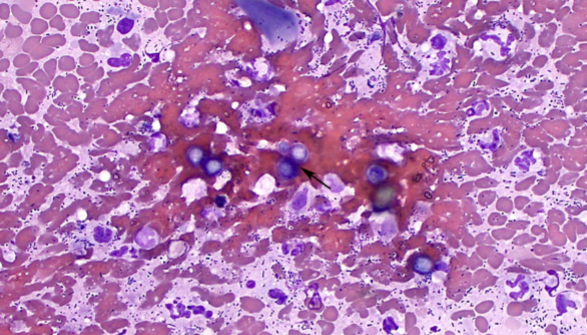

How do you identify Hepatozoon spp.: H. canis and H. americanum

INTRAcellular – malaria-like pill-shaped inclusions inside neutrophils and monocytes (WBCs)

what are the 2 forms of Hepatozoon spp.: H. canis and H. americanum

Gamonts and Schizonts

What does Hepatozoon spp.: H. canis and H. americanum cause

Subclinical to fever, depression, and bone disease